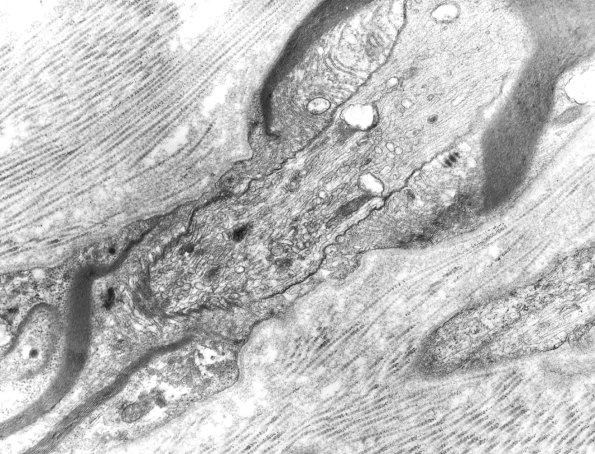

Washington University Experience | PERIPHERAL NEUROPATHY | 3 NORMAL MYELIN & SCHWANN CELLS | 2 Node of Ranvier | 16A Normal nerve, Node of Ranvier EM 1 - Copy

Accumulation of axonal subcellular organelles at normal nodes may suggest axonopathy. (electron micrograph)